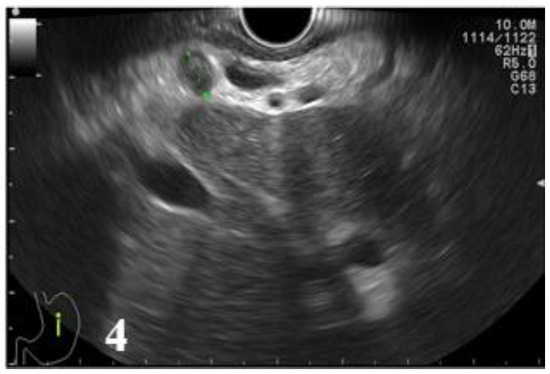

Figure 4.

EUS image showing a round lymph node with preserved hilum, with a diameter under 10 mm, located in the hepatic hilum.